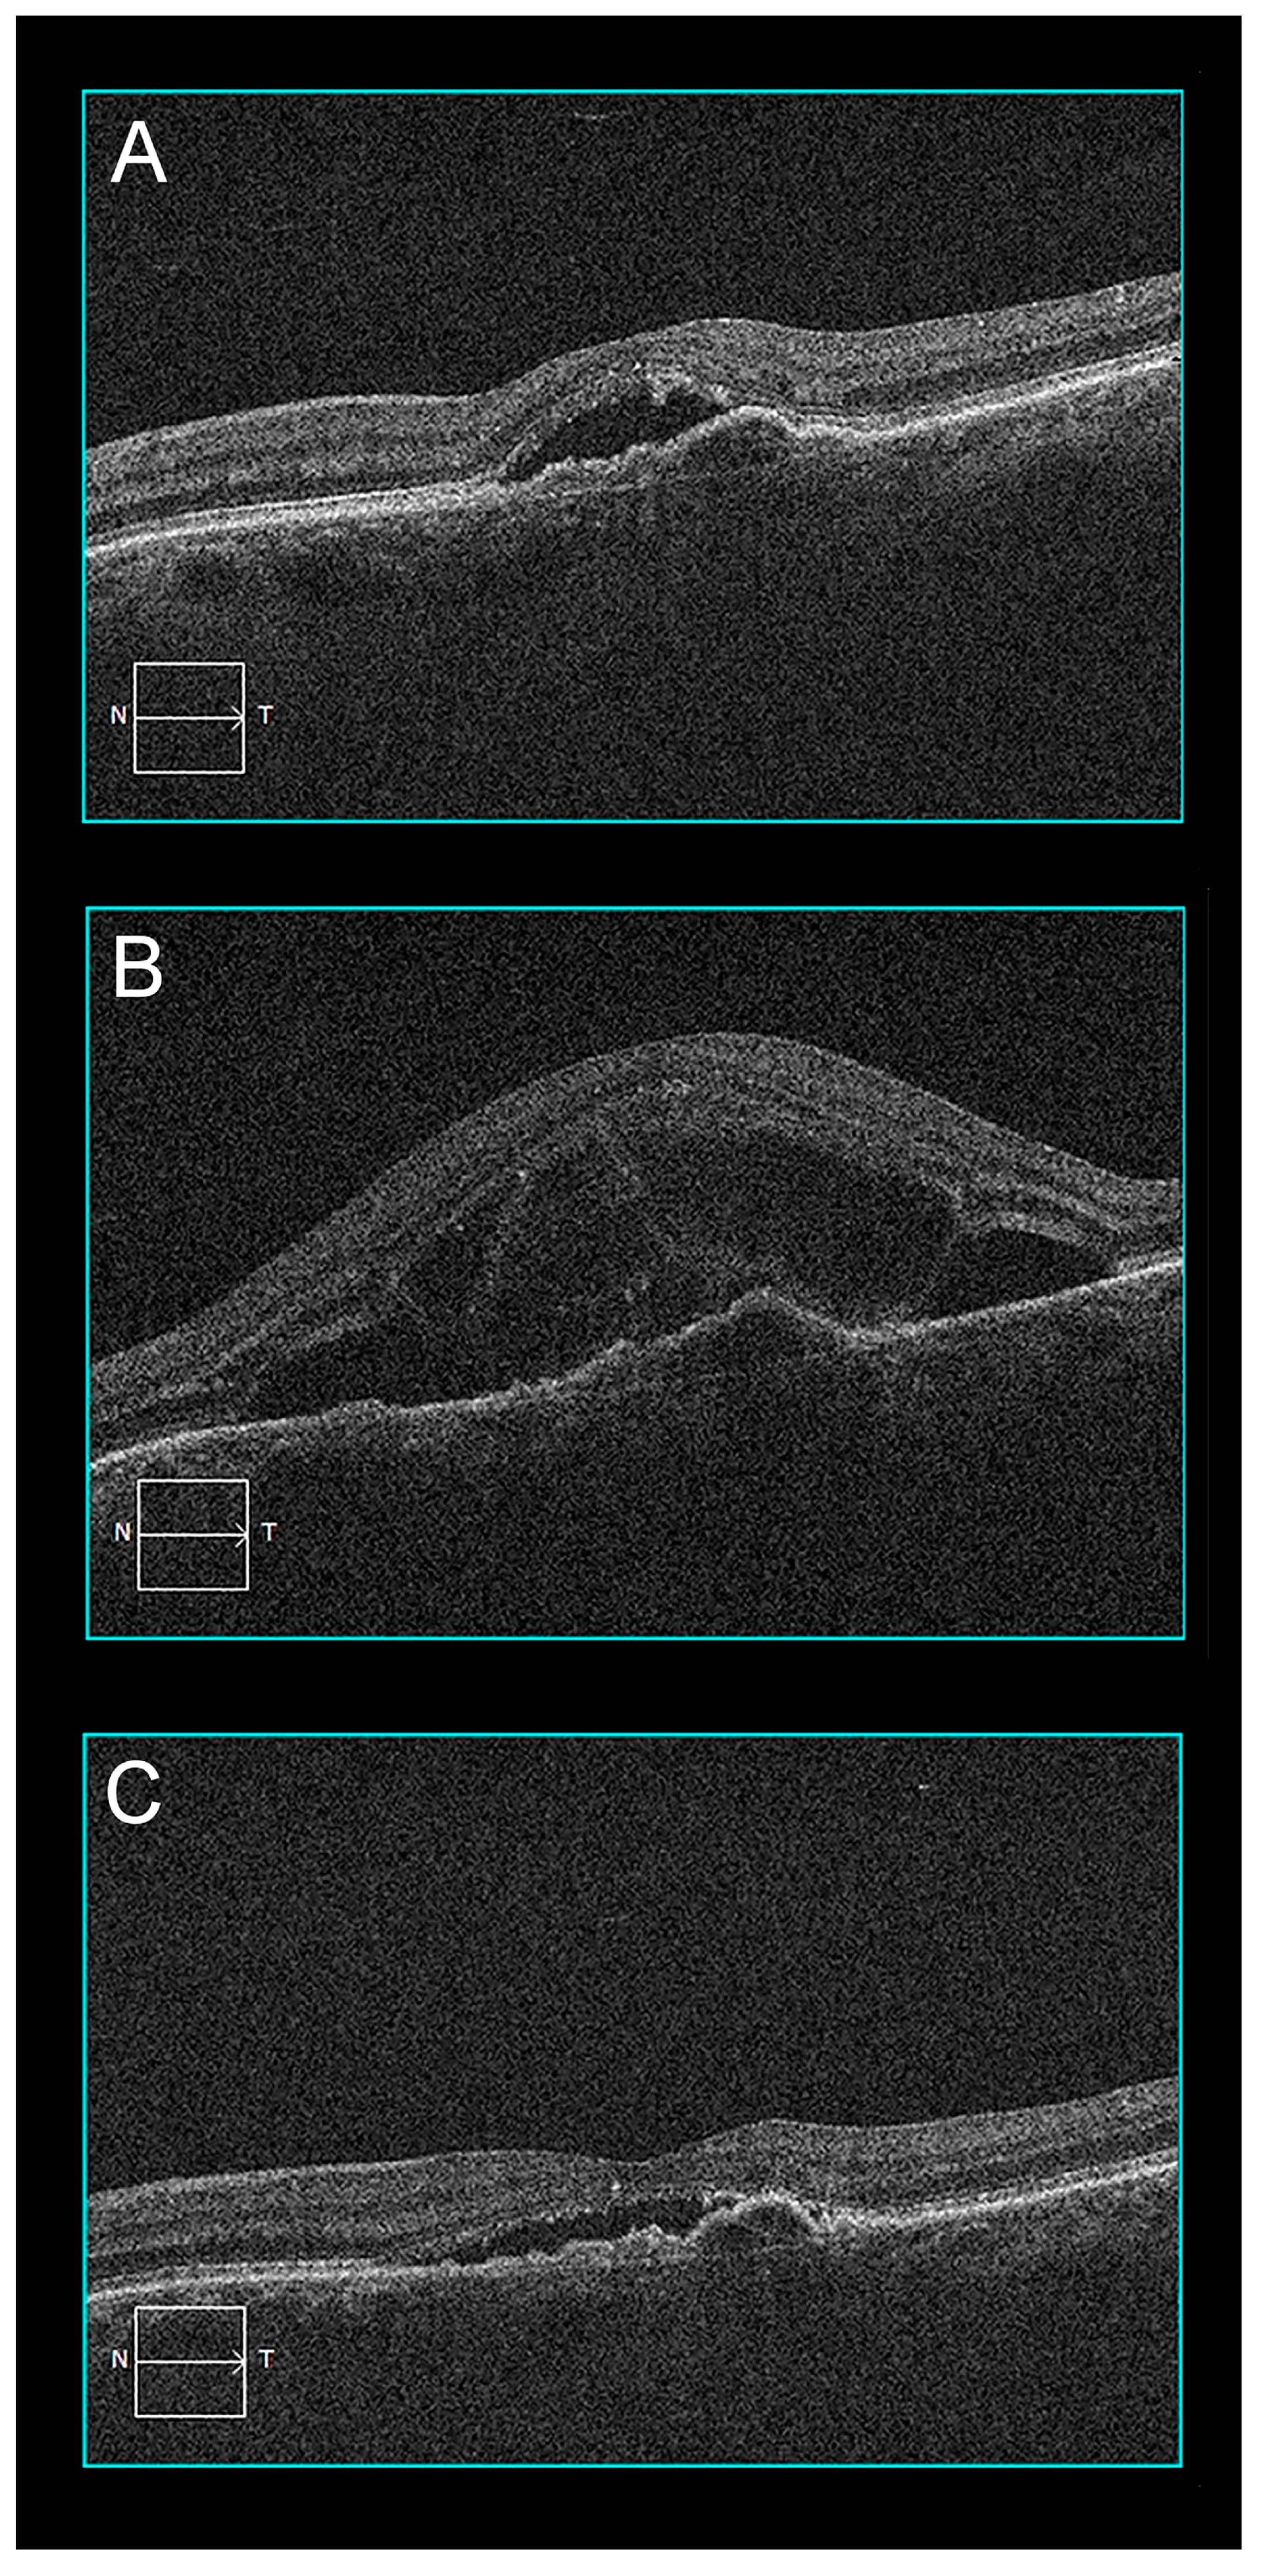

2.3. Case 3